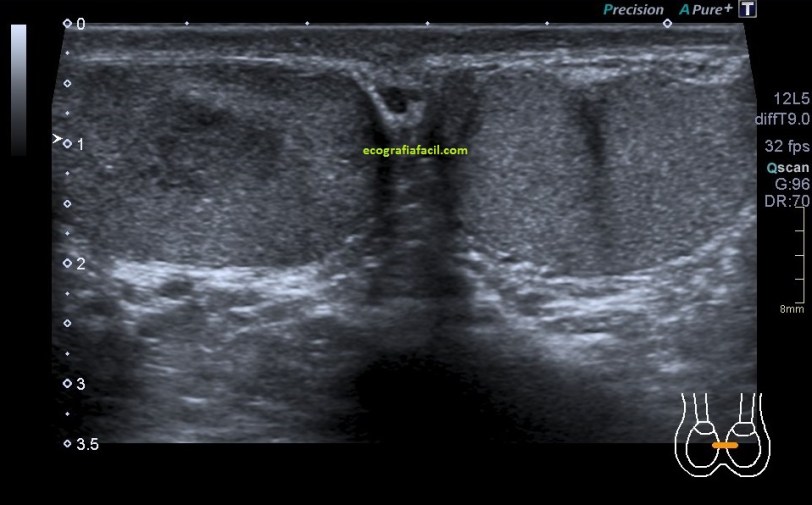

En algunas ocasiones podemos encontrarnos esto:

Compara la imagen 1 y la 2, grábala en tu memoria fotográfica. Ambas son unas imágenes en corte longitudinal del teste derecho de dos pacientes distintos.

Una vez que hemos encontrado la lesión, es momento de estudiarla detenidamente, su aspecto, tamaño bordes y vascularización son vitales para que la radióloga pueda efectuar un informe.

El aspecto de esta lesión, su semiología ya la has visto en estos dos casos diferentes, pero tienen en común, de modo general, hipoecogenicidad, heterogenicidad, bordes irregulares, con aspecto polilobulado y de tamaño y número variable.